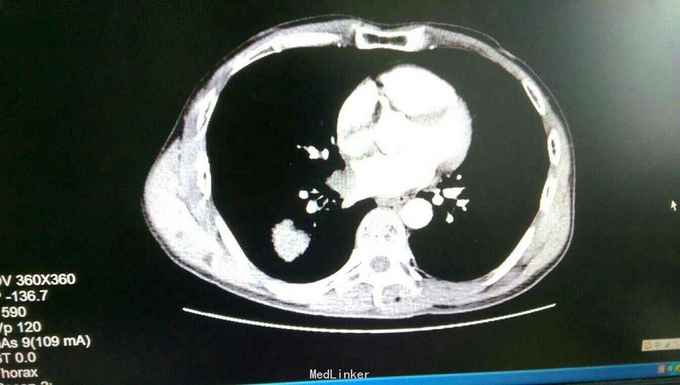

患者入院后,拟行左颌下肿块切除,在术前检查,术前准备时,常规胸片发现右侧肺部肿块,进一步行颈部及胸部ct检查,提示左颌下淋巴结肿大,转移性可能。右下肺周围性肺癌伴右肺门及纵膈多发淋巴转移考虑。决定先行左颌下肿块切除,明确诊断。术后病理示:左(左颌下腺)淋巴结转移性癌,来源首先考虑为肺。患者及家属考虑为晚期肿瘤,拒绝进一步手术治疗及化疗,下颌部切口愈合拆线后,出院。

患者出院后,门诊服中药治疗,定期复查。 讨论:患者因左颌下肿块前来就诊,术前检查发现肺部肿块,一元论考虑,应为肺部肿瘤转移所致。而且手术后病理亦证实。关键当下颌部出现肿块,应考虑肿块性质的鉴别。1.应考虑颌下肿块与颈部淋巴结的鉴别,尤其是无痛性肿块,要和淋巴结核及肿瘤等鉴别。2要和周围组织的肿瘤如甲状腺,鼻咽癌等浸润转移鉴别。3.要考虑纵膈,肺等远处转移。该患者为右下肺肿瘤已向纵膈及颈部,颌下转移,但患者临床表现仅有左颌下肿块,无胸闷气急,无咳嗽咳痰,虽ct检查发现纵膈及颈部多发淋巴结肿大,患者却无上腔静脉回流受阻,颈部浅表淋巴结未能扪及。该病例提示我们,当患者颈部出现肿块,应仔细检查,多些鉴别,以免漏诊。